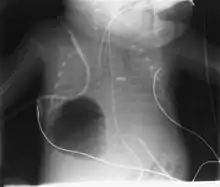

Large, right lower lobe pneumatocele is shown, compromising ventilation in a premature infant with RDS and superimposed RSV pneumonitis.

Diagnosis can be made using chest X-ray; the lesion shows up as a small, round area filled with air.[1] Computed tomography can give a more detailed understanding of the lesion.[1] Differential diagnoses – other conditions that could cause similar symptoms as pneumatocele include lung cancer, tuberculosis,[7] and a lung abscess[1] in the setting of hyper IgE syndrome (aka Job's syndrome), as a complication of COVID-19 pneumonitis,[8] or on its own, often caused by Staphylococcus aureus infection during cystic fibrosis.